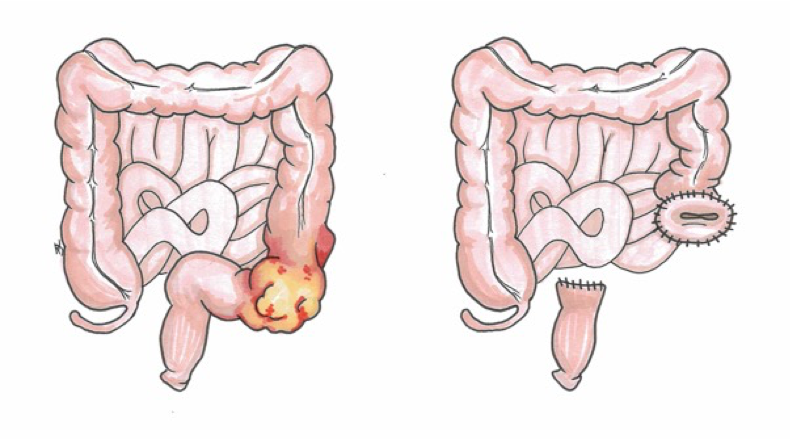

Sigmoid colon tumour obstruction

- MassâŠâŠ Resection